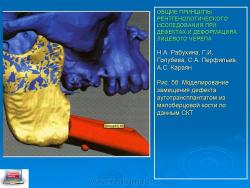

При СКТ исследованию подвергают реципиентные зоны (подвздошные кости, малоберцовую кость, ребра и т. д.) для определения точных размеров аутотрансплантатов, локализации отверстия питающих сосудов. В дальнейшем по данным СКТ осуществляется моделирование замещения костных дефектов, определяют локализацию остеотомии, углы соединения фрагментов трансплантата. Это существенно облегчает хирургу осуществление оперативного вмешательства, ускоряет его, позволяет прогнозировать и оптимизировать результаты (рис. 5 а, б). Использование СКТ обязательно при посттравматических деформациях носо-скулоорбитальной зоны, поскольку они очень часто сопровождаются повреждением дна орбиты и пролабированием окологлазных тканей или глазного яблока в верхнечелюстную пазуху, в результате чего возникают энофтальм и диплопия. Только поданным СКТ можно рассчитать те пластические мероприятия, которые необходимо предпринять для устранения этих симптомов. Восстановление целости орбитального дна и устранение смещения глазного яблока осуществляются помощью одно- или многослойных костных трансплантатов, которые выкраиваются из наружной костной пластинки теменной кости (рис. 6 а, б, в). СКТ необходима также для оценки состояния глазного нерва и глазодвигательных мышц. Алгоритм рентгенологического исследования пациентов с посттравматическими деформациями должен быть индивидуальным по сочетанию различных рентгенологических методик. Обработку результатов СКТ также необходимо осуществлять по индивидуальной схеме, в которой комбинируется анализ реформатированных изображений и трехмерного объемного воспроизведения. Для получения стереолитографических моделей (рис. 7) методом быстрого прототипирования нужны сканы в аксиальной проекции. Замещение обширных дефектов альвеолярных отростков костными аутотрансплантатами обычно сопровождается и восстановлением функции зубных рядов путем протезирования с использованием металлических имплантатов, вживляемых во вновь созданные аналоги альвеолярных отростков. В этих случаях перед имплантацией необходимо СКТ исследование для точного определения высоты, ширины и «плотности» костной ткани.

Рис. 5б.Моделирование замещения дефекта аутотрансплантатом из малоберцовой кости по данным СКТ